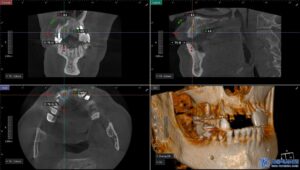

무절개 임플란트는 컴퓨터 분석을 통해

미리 계획된 경로를 따라 식립하기 때문에

절개가 필요하지 않고 출혈이 적으며

회복 속도가 빠릅니다.

특히 임플란트 성패에 중요한

식립각도에 관한 연구도

뉴스로 발표된바 있습니다.

또한, 위 사진처럼

수술가이드를 제작하여 오차 없이

정밀한 위치에 임플란트를

심을 수 있기 때문에

성공률도 높아지게 됩니다.